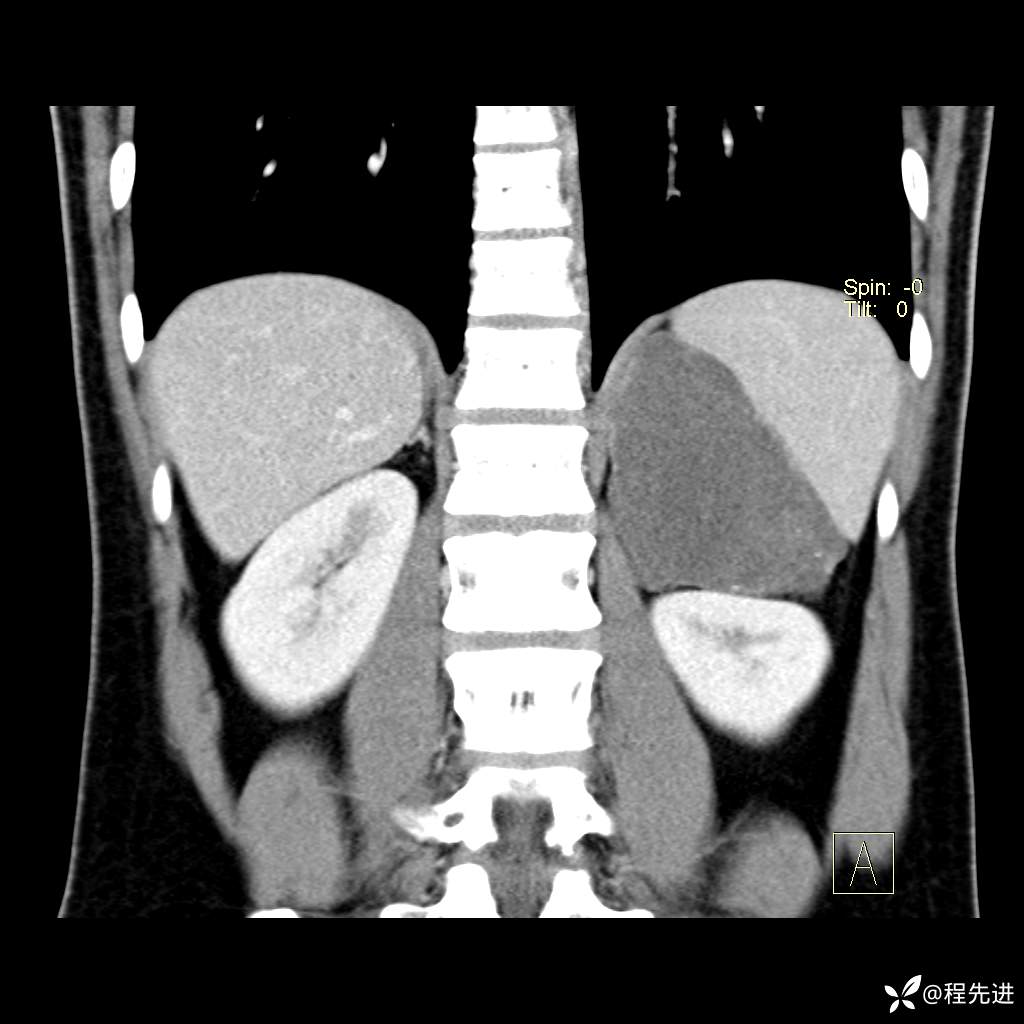

CT平扫:(CT值:平扫,27HU,动脉期,27HU,门静脉期,31HU,平衡期,32HU)

冠状位重建: